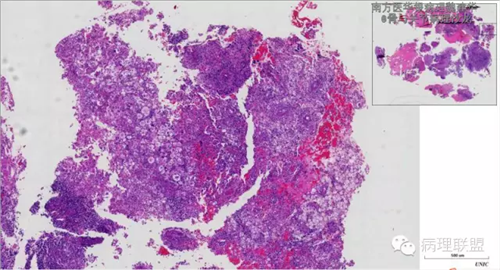

来源于组织细胞的相似性骨病ECD vs RDD 看图说话

病例由南方医华银病理魏建华提供,致谢。